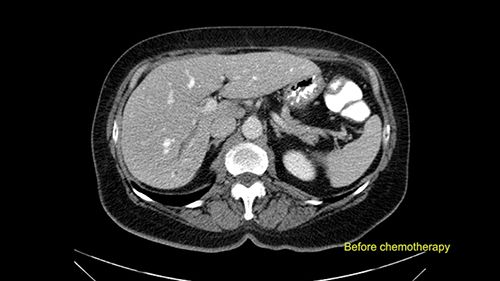

In this patient with multiple synchronous liver metastases that are small in nature, I’m very careful to ensure that I review not just the most recent CT scans but also all of the original CT scans from the time the patient declared with liver metastases so I can locate the original positions of the tumors, I can see the response to chemotherapy, and to ensure that I evaluate all of the areas where the tumors initially were present at the time of surgery to decide whether or not they need to be removed at the time of surgery.

In addition, as I plan this operation, I will also look at the size of the small tumors. They’re very small, some are less than one centimetre in size, and carefully evaluate the relationship between the small tumors and the surrounding vascular structures. If I cannot see or feel the tumors at the time of surgery, I will use the blood vessels in order to landmark and plan my operation.

![[before chemo]](jpg/preop_aw_moment8.jpg)